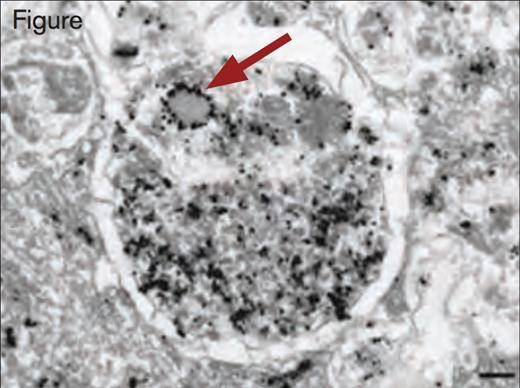

Immunogold Detection of vWF Protein in a Weibel–Palade Body Within an Autophagosome. Scale bar, 200 nm. Reprinted by permission from Macmillan Publishers Ltd: Nature Medicine. 2013; 19(10):1282, Copyright 2013.

By use of immunoelectron and immunofluorescence microscopy, the authors observed that Weibel–Palade bodies and autophagosomes are located in cultured human umbilical vein endothelial cells (HUVECs) in closer proximity than expected by chance. Additionally, they observed that Weibel–Palade bodies and autophagosomes are occasionally found fused together. Additional immunoelectron microscopy using anti-vWF antibodies revealed the presence of vWF in autophagosomes. Lentiviral shRNA-mediated knockdown of the autophagy genes, Atg7 and Atg5, in HUVECs produced several abnormalities on vWF expression. Although the intracellular concentration of vWF was not reduced, the ratio of pro-vWF to mature vWF was significantly increased in Atg7 or Atg5 knockdown cells. Stimulated release of vWF by histamine or vascular endothelial growth factor was reduced. Two inhibitors of autophagosome function, chloroquine and bafilomycin, blocked stimulated release of vWF from HUVECs. Additionally, the number and size of Weibel–Palade bodies was decreased in Atg7 and Atg5 knockdown cells, as well as in cells treated with chloroquine or bafilomycin. The rate of exocytosis of Weibel– Palade from endothelial cells was also decreased in Atg7 knockdown cells compared with normal HUVECs.